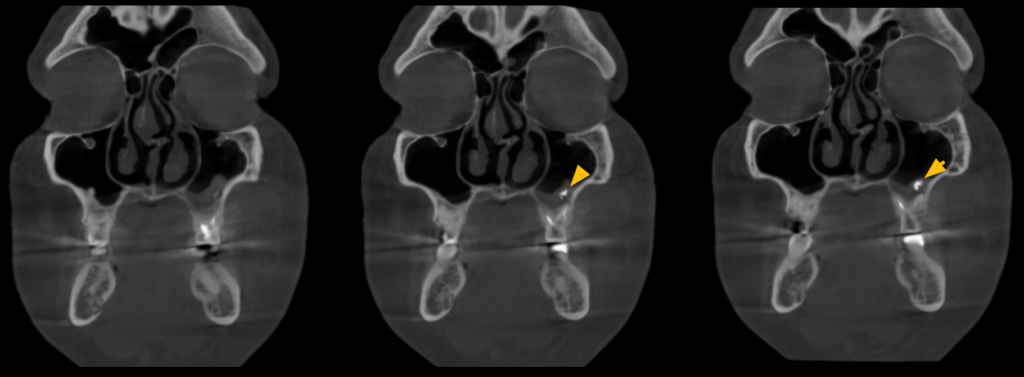

Paciente masculino de 45 años acude para una evaluación general. A la evaluación de la radiografía panorámica (Figura 1) se observa engrosamiento de la mucosa de seno maxilar izquierdo además de una imagen radiopaca proyectada en seno maxilar izquierdo; así mismo en pieza 26 se observa restauración coronaria, sellado cameral y obturación de conductos. A la evaluación de la tomografía volumétrica (cone beam) bimaxilar en los cortes axiales (Figura 2), coronales (Figura 3) y transaxiales (Figura 4) se observa que la pieza 26 presenta obturación de conductos además del engrosamiento de seno maxilar izquierdo e imagen hiperdensa de alta densidad, de

forma irregular, localizada en la mucosa de seno maxilar izquierdo.

CORTES CORONALES